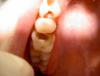

Ico Опубликовано 22 февраля, 2013 Поделиться Опубликовано 22 февраля, 2013 .Немного красок и совсем как свои Ссылка на комментарий

ger_berra Опубликовано 22 февраля, 2013 Поделиться Опубликовано 22 февраля, 2013 .Тут бугры лучше перекрыть. Ссылка на комментарий

anvladd Опубликовано 22 февраля, 2013 Поделиться Опубликовано 22 февраля, 2013 Тут бугры лучше перекрыть.не перекрыты только дист. щёчн. и дист нёбн.тут конечно коронка уже нужна. Ссылка на комментарий